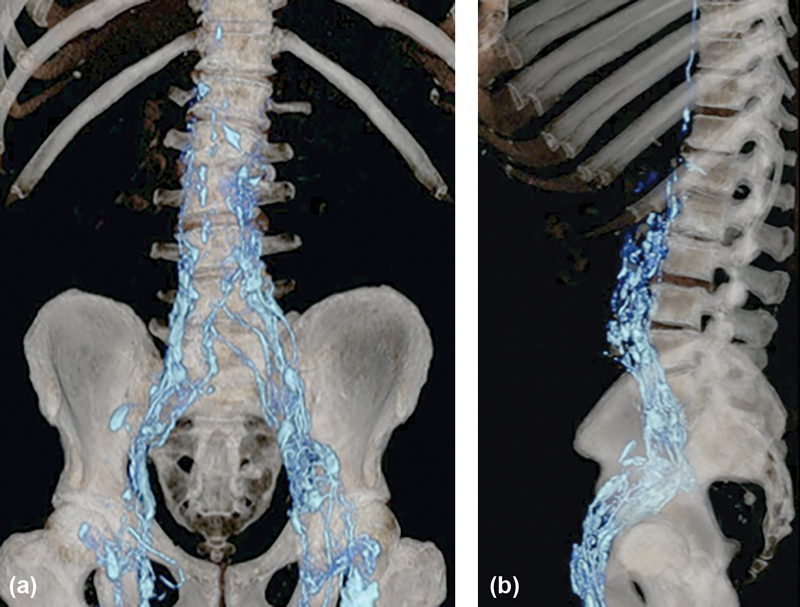

Fig. 3.

Volume-rendered CT lymphangiography in coronal ( a ) and sagittal ( b ) planes shows coalescing of lymphatic vessels along the pelvic sidewalls to the retroperitoneum overlying the spine.